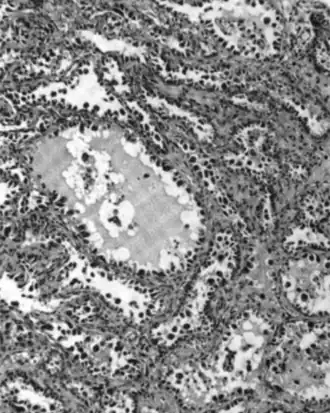

Serous carcinoma

.jpg)

Serous ovarian cancer is the most common type of epithelial ovarian cancer and it accounts for about two-thirds of cases of epithelial ovarian cancer.[28] Low-grade serous carcinoma is less aggressive than high-grade serous carcinomas, though it does not typically respond well to chemotherapy or hormonal treatments.[28] Serous carcinomas are thought to begin in the Fallopian tube.[70][71] High grade serous carcinoma accounts for 75% of all epithelial ovarian cancer.[69] About 15–20% of high grade serous carcinoma have germline BRCA1 and BRCA2 mutations.[69] Histologically, the growth pattern of high grade serous carcinoma is heterogenous and has some papillary or solid growth patterns.[69] The tumor cells are atypical with large, irregular nuclei.[69] It has a high proliferation rate.[69] 50% of the time, serous carcinomas are bilateral, and in 85% of cases, they have spread beyond the ovary at the time of diagnosis.[72]

Serous Tubal Intraepithelial Carcinoma (STIC) is now recognized to be the precursor lesion of most so-called ovarian high-grade serous carcinomas.[72] STIC is characterised by

- Abnormal p53 staining

- Ki67 proliferation index in excess of 10%

- Positive WT1 (to exclude metastases)[72]